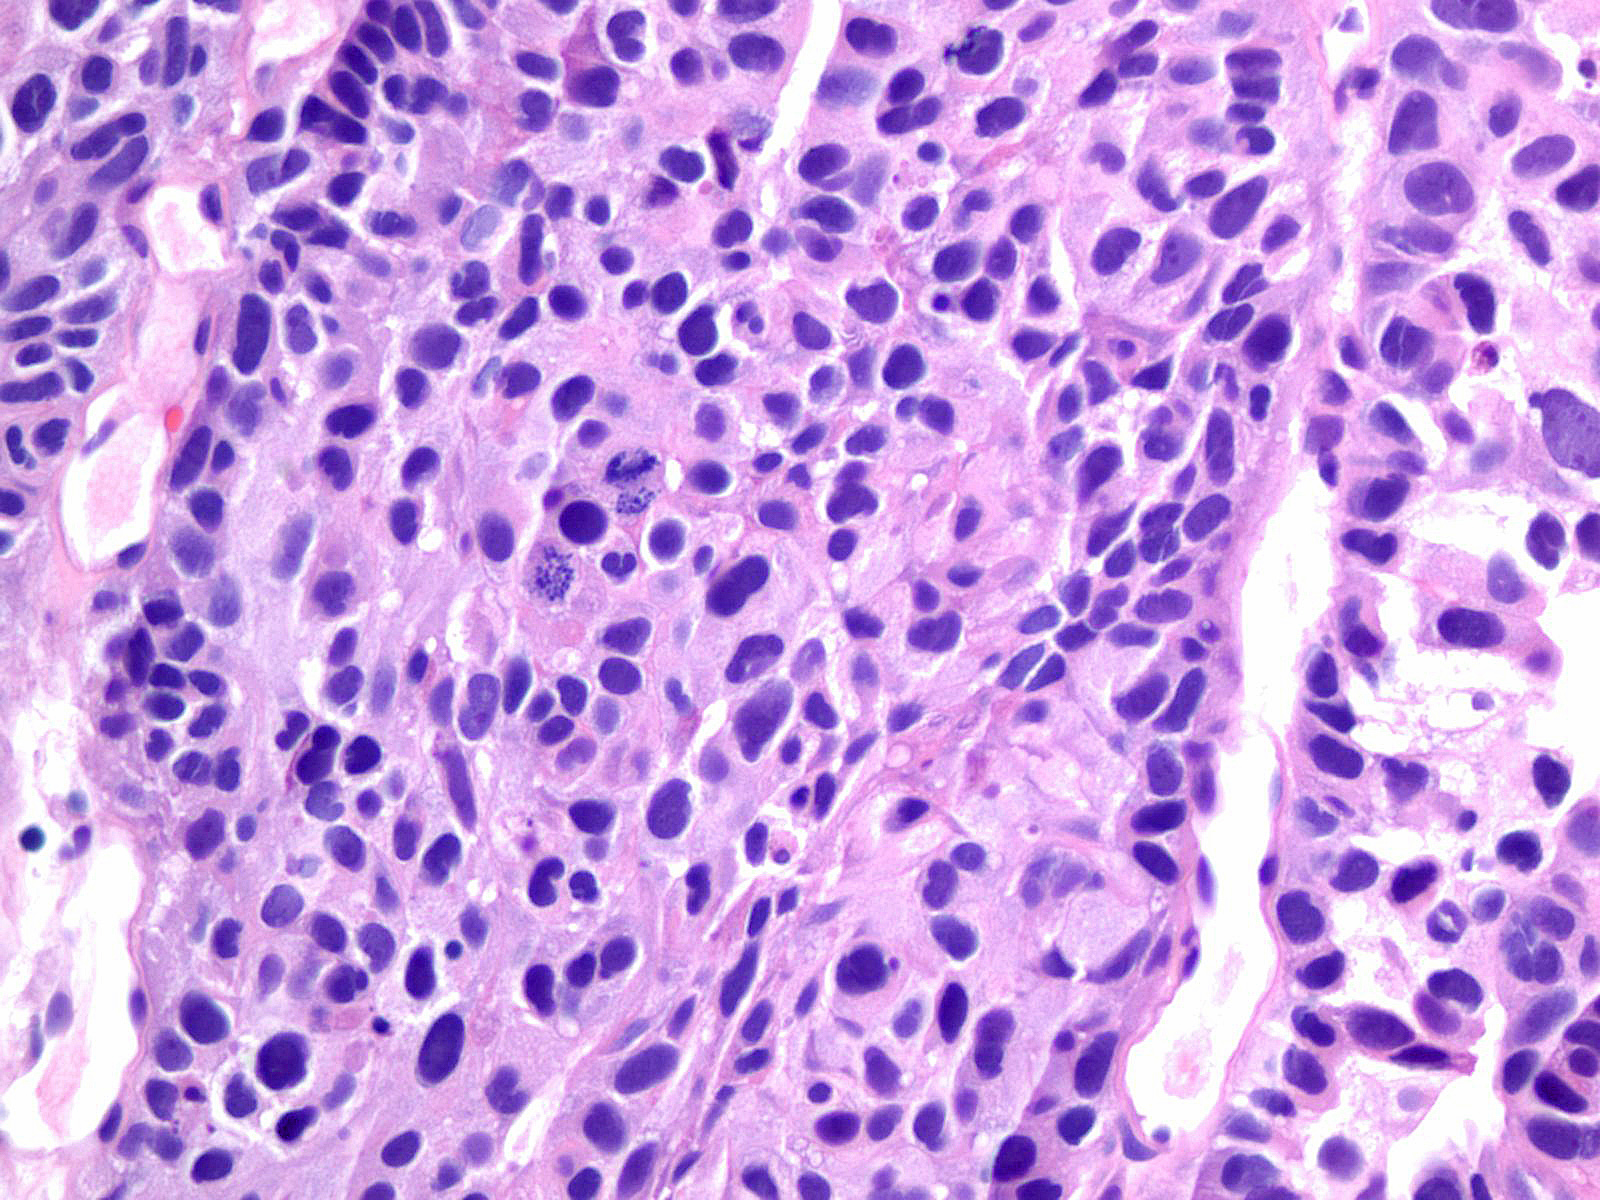

Consensus grade: High-grade papillary urothelial carcinoma (HG-PUC)

Lesion shows marked variation in nuclear size, shape and chromatin. Architecturally, cells appear irregularly clustered and the epithelium is disorganized. Mitotic figures are frequently seen at all levels.